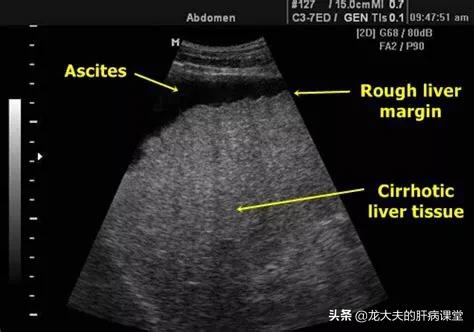

出现腹水的肝病,一般属于肝硬化失代偿期。肝硬化失代偿期的终末阶段,会伴有各种各样的并发症,不是说有腹水就可以确定是肝硬化晚期。这些并发症包括严重感染、肝性脑病和上消化道出血,等等。

腹水的治疗:腹水的治疗,包括抽腹水、利尿,以减轻压迫症状。同时,要使用抗感染药,针对可能的病原体,使用抗菌药或者抗真菌药等。

营养支持治疗:腹水的一个重要原因是白蛋白降低,白蛋白主要是肝细胞合成的。在肝功能减退到一定程度之后,白蛋白的合成减少,这个时候需要额外的补充白蛋白,可以利尿治疗。利尿也是要腹水治疗的重要措施之一。